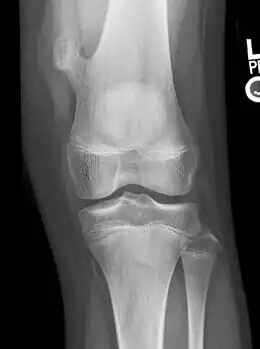

-

Osteochondroma arising from the thigh bone, near the knee -